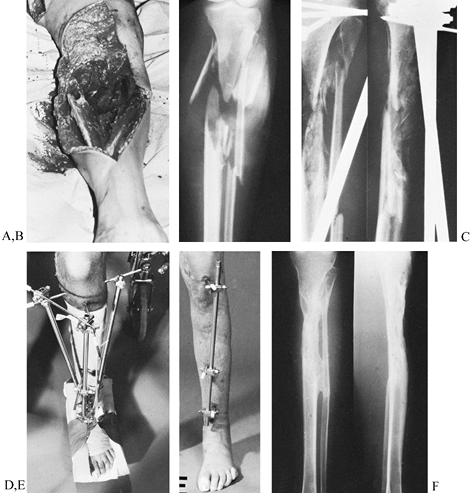

Figure 11.21. A gunshot wound involving the lateral aspect of the proximal tibia with severe loss of soft tissue and bone. A: Initial appearance from the lateral side. B: Stabilization by an external fixator placed on the medial side. C:

The soft-tissue defect covered by a lateral gastrocnemius flap; there is no interference from the fixator frame. A split-skin graft was used to cover the muscle flap. D: Radiographs at this stage. E: Elevation of the healed gastrocnemius flap to allow the skeletal defect to be bone grafted. F: At 5 months, the fracture has healed, and the patient has borne full weight for 4 weeks. G: Radiographs 1 year after the injury. (From Behrens F, Searls K. External Fixation of the Tibia: Basic Concepts and Prospective Evaluation. J Bone Joint Surg Br 1985;68:246, with permission.) |